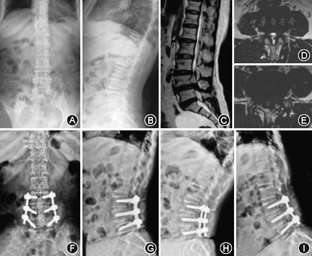

两组术前Coflex植入节段椎间隙高度、椎间孔高度、椎间孔宽度和ROM差异无统计学意义(P>0.05)。Topping-off组椎间孔高度、椎间孔宽度、椎间隙高度术后1年随访较术前显著增加,但末次随访相比术后1年显著降低,与术前无显著性差异。融合组椎间隙高度、椎间孔高度和宽度在术后各随访时间点无显著性改变。融合组术后椎间活动度显著性降低(P=0.000)(图2,图3)。

末次随访Topping-off组上位邻近节段椎间孔高度和椎间隙高度较术前降低,但是两组间差异无统计学意义(P>0.05)。融合组上位相邻节段末次随访椎间孔高度、椎间隙前缘高度和椎间隙后缘高度较术前显著性降低(P=0.000, P=0.000,P=0.003),并且ROM由术前的(4.4±2.7)°显著性的增加到(5.4±2.2)°(P=0.000)。末次随访对两组患者下位邻近节段各指标与术前差异无统计学意义(P>0.05)。

末次随访Topping-off组8例(13.3%)ASD,而融合组18例(26.5%)ASD,两组差异有统计学意义(P=0.033)(表3)。27例(21/26)出现上位ASD较5例下位ASD(5/26)显著性的增加(P=0.042)。手术方式和术前椎间盘Pfirrmann分级Ⅲ级或以上是ASD发生的危险因素,融合组ASD发生率是Topping-off组发生率的4.452倍(P=0.018, 95%CI 1.145~16.302)(表4)。年龄>55岁、男性、椎间盘Pfirrmann分级Ⅲ级或以上和BMI<25的患者术后ASD发生率高,但差异无统计学意义。